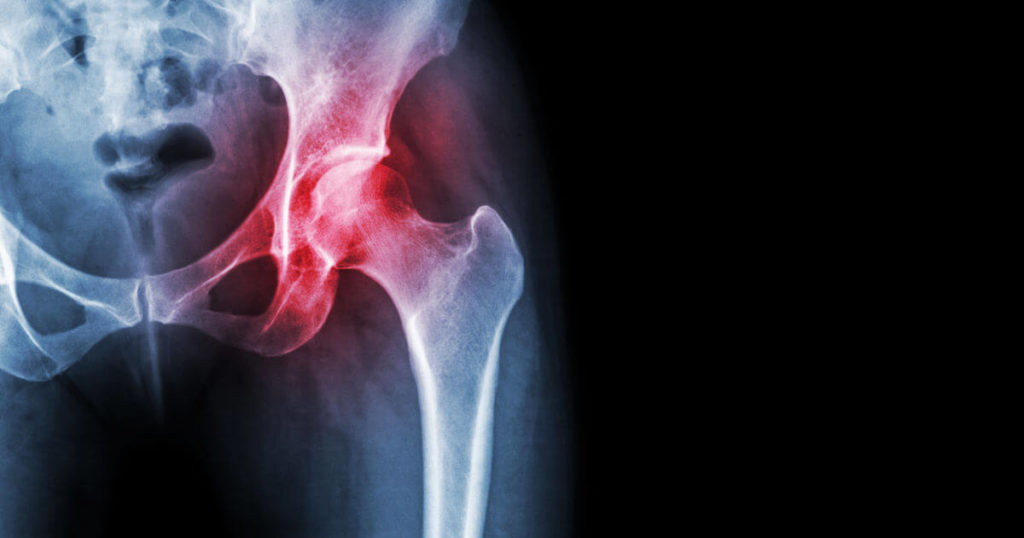

«La chirurgia protesica dell’anca – spiega Carlo Doria – permette di intervenire nei casi più avanzati di degenerazione dell’articolazione per i quali sono controindicati oppure non hanno avuto successo i trattamenti conservativi. Nella sua forma corrente, la sostituzione totale dell’anca è una delle operazioni di maggior successo della moderna chirurgia ortopedica poiché consente ai pazienti, affetti da patologie invalidanti, di migliorare la qualità di vita ripristinando la funzionalità articolare e abolendo la sintomatologia dolorosa».